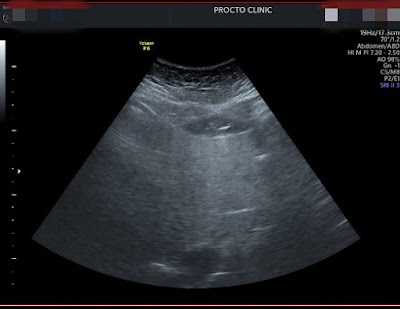

附上一張超音波,雖然不是很懂,但醫師說是重度脂肪肝,真的是雙重驚嚇,所以考慮沒多久,就決定要做胃肉毒。